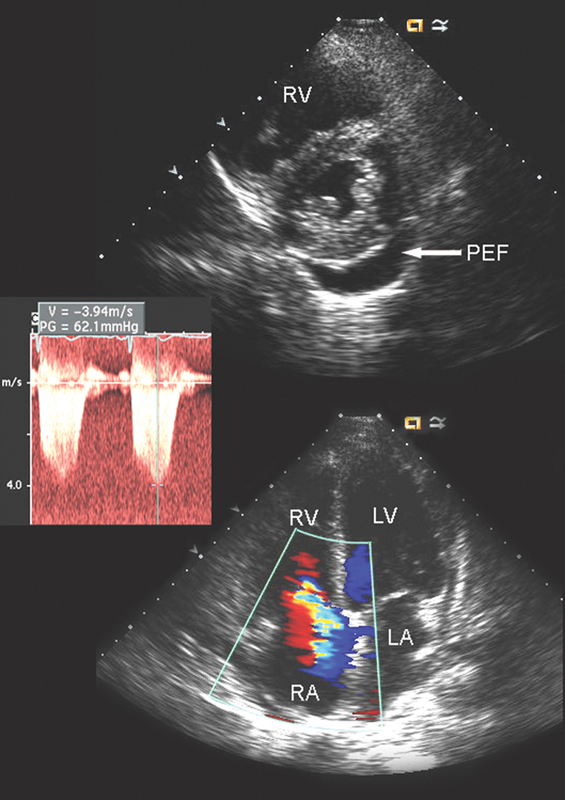

فحوصات تشخيصية لبعض امراض القلب والشرايين التاجية